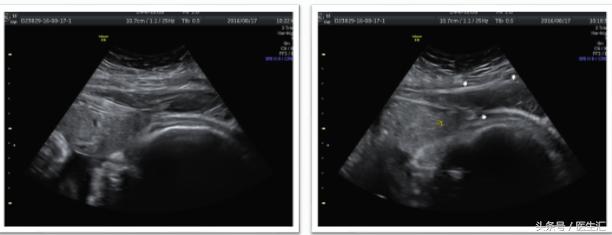

8月17日倒手续复查超声:B超提示宫体下段右前壁(切口处)部分肌层未显示,该处可见部分胎盘达浆膜层,宫体下段前方另见2.5cmX9.1cmX10.4cm低回声(血肿);羊水过多。